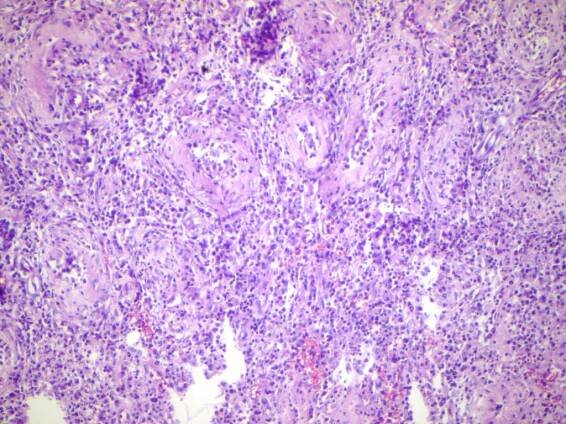

Chronic epididymitis is a form of epididymitis that persists for more than three months. Chronic epididymitis is characterized by inflammation even when there is no infection present.